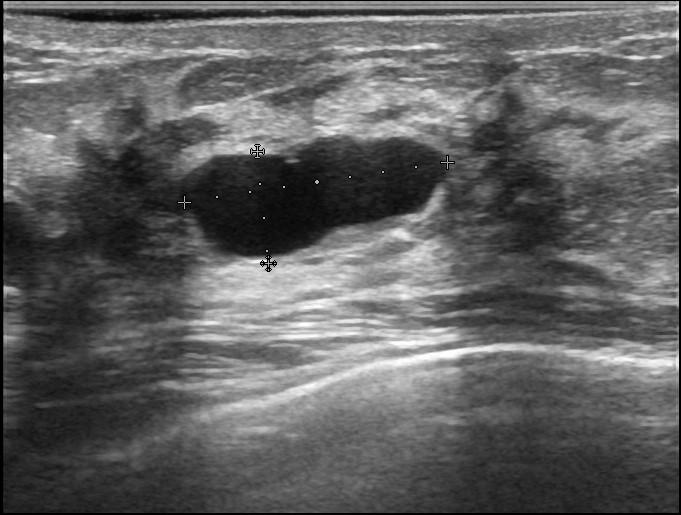

Рис.6 Эхограмма кисты молочной железы

Серошкальный В-режим, с помощью которого врач видит строение вашей молочной железы и может выявить патологические изменения, оценить форму, контур и структуру образования.